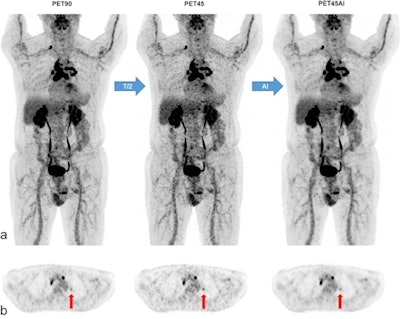

Next, the researchers performed two PET reconstructions: one for routine clinical purposes using the full acquisition time of 90 seconds per bed position ("PET90"), and a second one using 45 seconds per bed position ("PET45AI"), with reconstruction performed by the algorithm.

Five experienced nuclear medicine physicians reviewed the PET90 and PET45AI images side-by-side, and attributed a global, whole-image quality score to each PET series (1 = poor; 2 = moderate; 3 = good), as well as evaluated cancer lesion detectability.

According to the results, image quality scores were similar between original PET90 and PET45AI, with both receiving good scores in 92% of exams and moderate scores in 8% of exams.

A 77-year-old man (78 kg; BMI 24 kg/m2) with multifocal lymphadenopathy of unknown origin. MIP views (a) and axial PET slices (b) of F-18 FDG PET90, PET45, and PET45AI. Detection of small left suprahilar lymphadenopathy in all PET series (vertical arrows in b) with respective standard standardized uptake value corrected for lean body mass (SULmax) of 1.8 (PET90), 2.3 (PET45), and 1.7 g/ml (PET45AI). Nonetheless, PET45 images are noisier than PET90 or PET45AI images, particularly in the liver. Image courtesy of the European Journal of Nuclear Medicine and Molecular Imaging.Concerning lesion detection, 33 out of 195 patients presented a normal and concordant examination on both PET series. In the remaining 162 patients, a total of 856 lesions were detected. Of these 856 lesions, the reviewers visualized 836 lesions in both original PET90 and denoised PET45AI scans, which resulted in a lesion concordance rate of 97.7%.

"AI allows F-18 FDG-PET duration in digital PET/CT to be halved, while restoring degraded half-duration PET image quality," the researchers wrote.